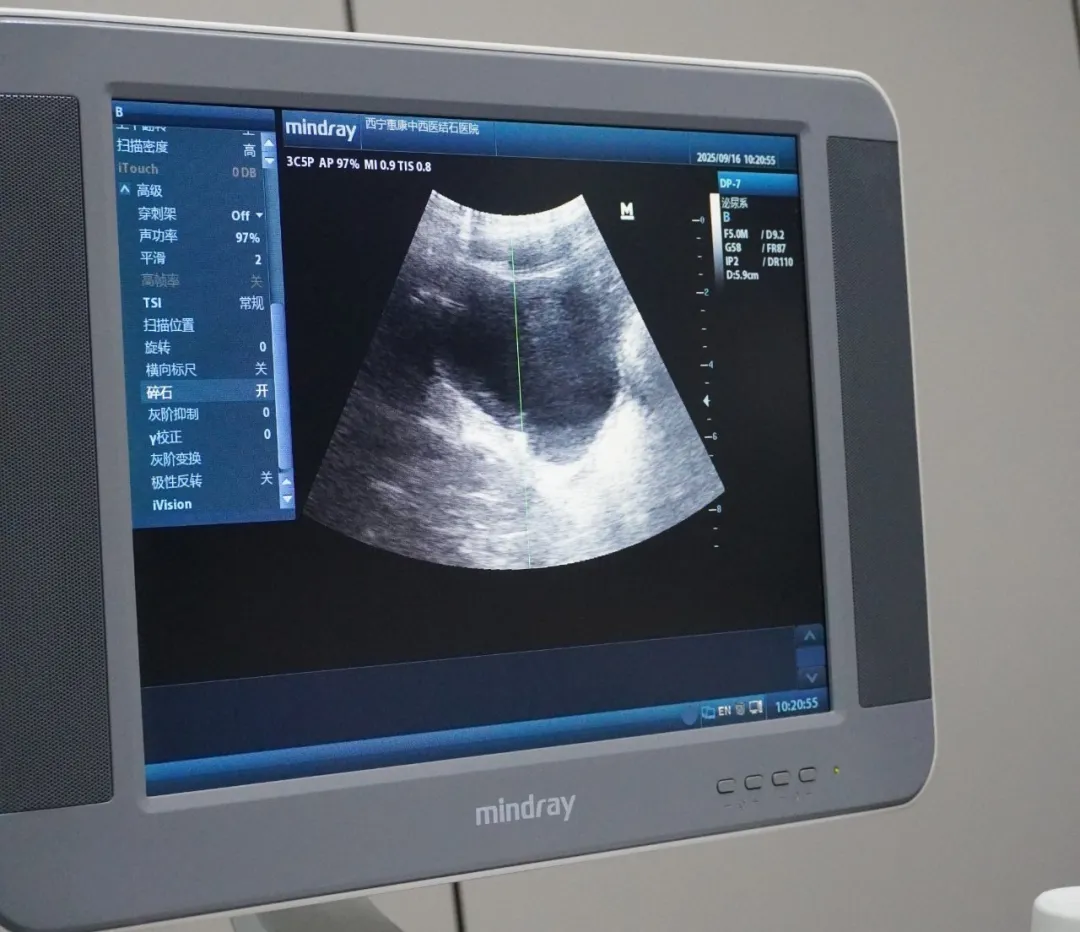

治疗过程中,医护团队严格按照操作规范执行,通过实时监测设备参数,确保治疗方案的安全性与合理性,尽可能降低患儿的不适感。

十几分钟的时间,在大家的共同关注下悄然过去,而这场体外碎石治疗也顺利结束了。结束后的小男孩,仿佛一下子就摆脱了之前病痛带来的阴霾,又恢复了往日的活泼,那纯真的笑容再次绽放在他的脸上,也让在场的每一位医护人员都由衷地感到欣慰。